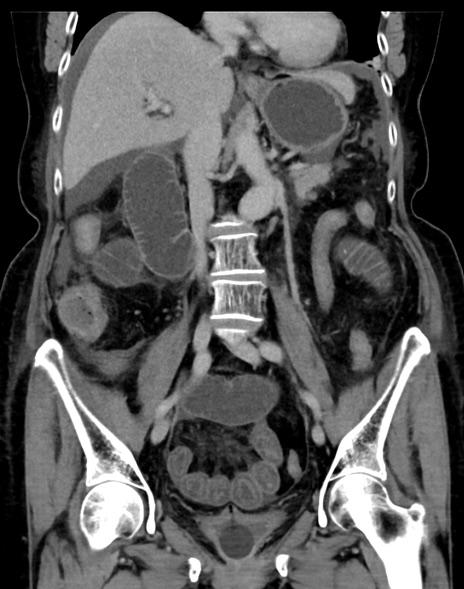

症例13 CT(冠状断像)1日半後